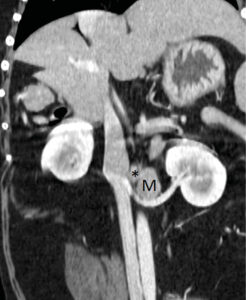

La tomografía computarizada (TC) es una técnica que va a emplearse habitualmente de forma previa a la cirugía en masas adrenales caninas, debido a que se considera más precisa que la ecografía para la detección de invasión vascular: tiene una sensibilidad y especificidad aproximada del 90 %28,29 (imagen 5) y esto es de gran importancia ya que, si existe invasión vascular, el abordaje quirúrgico será diferente.

Imagen 5. Imágenes de TC en ventana de tejidos blandos en fase venosa tras la administración de contraste reconstruidas en planos sagital (A) y dorsal (B) donde se observa un defecto de llenado de la vena cava caudal (círculo negro) por la presencia de una masa hipoatenuante de 4 cm de longitud que se corresponde con un tromoboembolismo tumoral a través de la vena frénico abdominal (*) por un feocromocitoma en la glándula adrenal izquierda (M).

Además, la presencia, el tamaño y la extensión del trombo van a tener un impacto sobre el pronóstico29. Recientemente se ha descrito un sistema de clasificación que puede ser de ayuda para determinar si existe o no invasión vascular, ya que en ocasiones puede resultar complicado porque, debido al gran tamaño de las masas, puede producirse una compresión vascular que dificulta la exploración29.